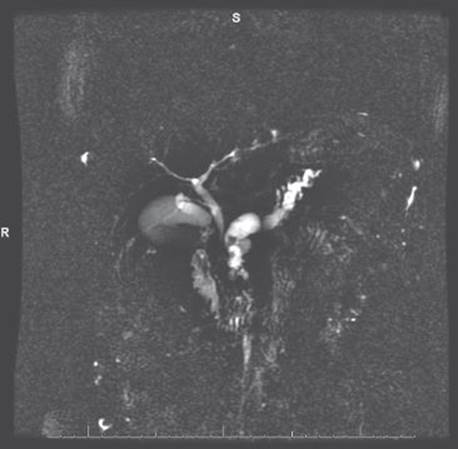

In the present patient, MRCP revealed a diffusely dilated main pancreatic duct with multiple intraluminal filling defects consistent with pancreatic duct stones (Figure 1).

FIGURE 1 • MRCP showing dilation of main pancreatic duct.